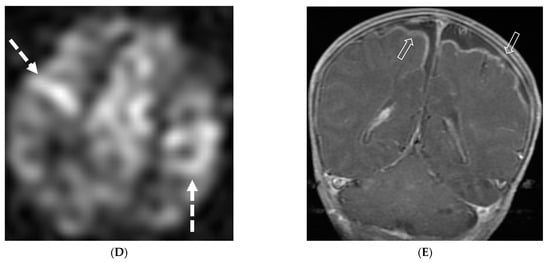

E. coli is another common neonatal and infantile cause of bacterial meningitis. There is characteristic diffusion restriction in the extra-axial collections along with ventriculomegaly and/or ventriculitis [74]. To note, extra-axial empyema is also common with S. pneumoniae, but occur in an older age group. Serratia marcescens and Citrobacter are two uncommon pathogens causing meningitis in neonates with fulminant disease course. They lead to large parenchymal abscesses with striated appearance on T2W images and foci of susceptibility. N. meningitidies causes typical gyriform cortical enhancement consistent with cerebritis predominantly involving the occipital lobes (Figure 12) [74].

Figure 12.

Axial DWI (A), axial SWI (B), sagittal T2 (C), axial ASL (D) and coronal T1 post contrast (E): 11-day-old female presented with seizures and lethargic. Restricted diffusion is noted in the sulci along the bilateral frontal convexities, concerning for meningitis (arrows). Curvilinear susceptibility in the extra-axial spaces of bilateral frontal convexities, consistent with thrombosed cortical veins (curved arrows). Cortical T2 hyperintensity is seen in the bilateral frontal and parietal lobes with corresponding hyperperfusion in keeping with extensive cerebritis (dashed arrows). Diffuse leptomeningeal and pachymeningeal enhancement is seen (open arrows). Overall features represent meningitis and cerebritis. Cerebrospinal fluid analysis: Group B streptococcus.